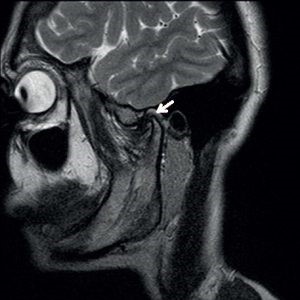

МРТ височно-нижнечелюстного сустава является важным инструментом для диагностики различных заболеваний и состояний, включая кисты. Врачи отмечают, что данное исследование позволяет получить детализированные изображения мягких тканей, суставов и костей, что особенно полезно при выявлении аномалий. Кисты, которые могут образовываться в области ВНЧС, часто являются безболезненными и не вызывают выраженных симптомов, однако их наличие может привести к дискомфорту и ограничению подвижности. Специалисты подчеркивают, что своевременная диагностика с помощью МРТ позволяет не только подтвердить наличие кисты, но и оценить ее размеры и влияние на окружающие структуры. Это, в свою очередь, помогает врачам разработать оптимальную стратегию лечения, что существенно повышает шансы на успешное восстановление функции сустава.

МРТ височно-нижнечелюстного сустава (ВНЧС) является важным инструментом для диагностики различных заболеваний и состояний, включая кисты. Многие пациенты отмечают, что процедура безболезненная и не требует специальной подготовки. На снимках МРТ можно четко увидеть структуру сустава, а также наличие аномалий, таких как кисты, которые могут вызывать дискомфорт или болевые ощущения. Врачи подчеркивают, что кисты ВНЧС часто являются доброкачественными образованиями, но их наличие требует внимательного наблюдения и, в некоторых случаях, лечения. Пациенты также отмечают, что результаты МРТ помогают им лучше понять свое состояние и принять обоснованные решения о дальнейшем лечении.

МРТ при кисте верхнечелюстной пазухи

При наличии подозрения на кисту верхнечелюстной пазухи врачи в обязательном порядке назначают пациенту МРТ челюсти. Киста представляет собой патологию, образуемую в области стенок гайморовой полости. Среди симптомов данного заболевания находится:

МРТ, проводимое в области челюстно-лицевого сустава при наличии кисты позволяет выявить стадию, а также характер течения данного заболевания. Чем раньше было проведено исследование, тем легче и быстрее будет выявить болезнь и вылечить ее.

Может ли возникнуть киста в ВНЧС?

Ганглионарные или синовиальные кисты ВНЧС встречаются редко . Обычно они встречаются у женщин среднего возраста и проявляются в виде преаурикулярного отека, часто с жалобами на боль. Пациентам с этими симптомами необходимо провести МРТ и/или УЗИ для анализа типа поражения.